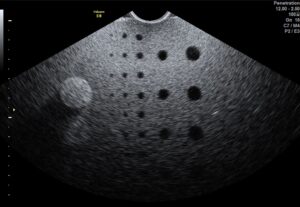

Après la remise en huile